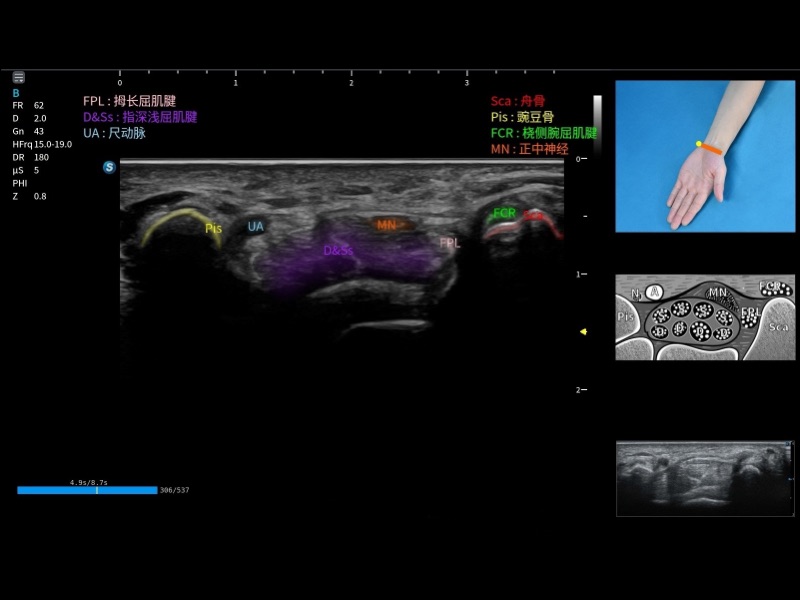

将测量、体标和注释等关键内容整合到一个页面中。精简界面,诊断更有针对性。

可助力简化工作流程,同时提升操作标准化程度,并减少按键次数,缩短检查时间。